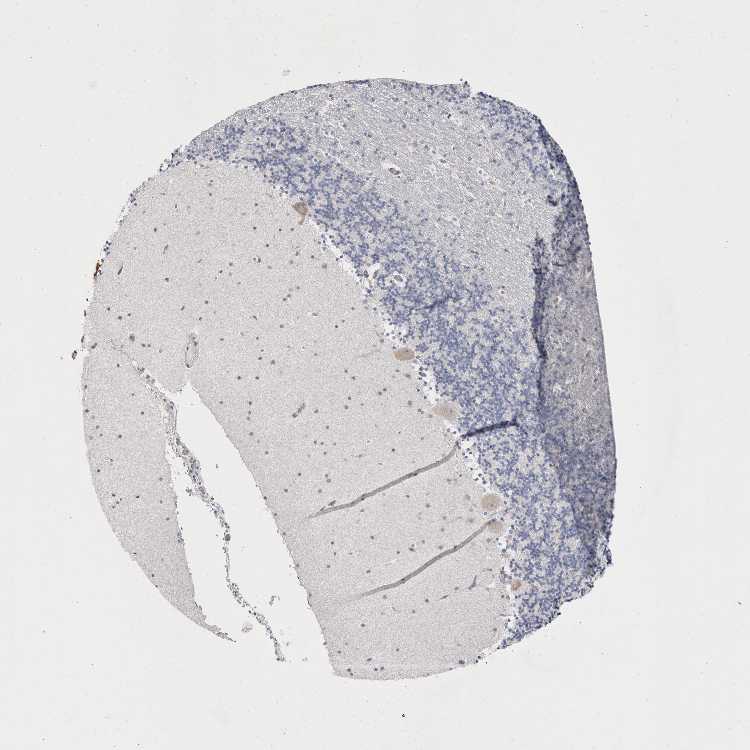

CEREBELLUM - Antibody stainingi

Antibody staining in the annotated cell types in the current human tissue is reported as not detected, low, medium, or high, based on conventional immunohistochemistry profiling in selected tissues. This score is based on the combination of the staining intensity and fraction of stained cells.

Each image is clickable and will lead to virtual microscopy that enables deeper exploration of all samples and also displays staining intensity scores, fraction scores and subcellular localization as well as patient and tissue information for each sample.

Antibody HPA026970Antibody HPA029126

Purkinje cells LowNot detected

Cells in granular layer Not detectedNot detected

Cells in molecular layer Not detectedNot detected